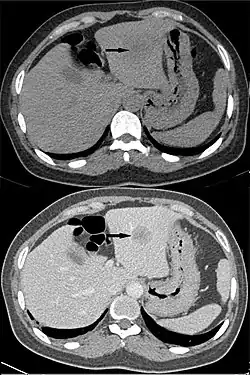

Hepatocellular carcinoma, without (top) and with (bottom) IV contrast